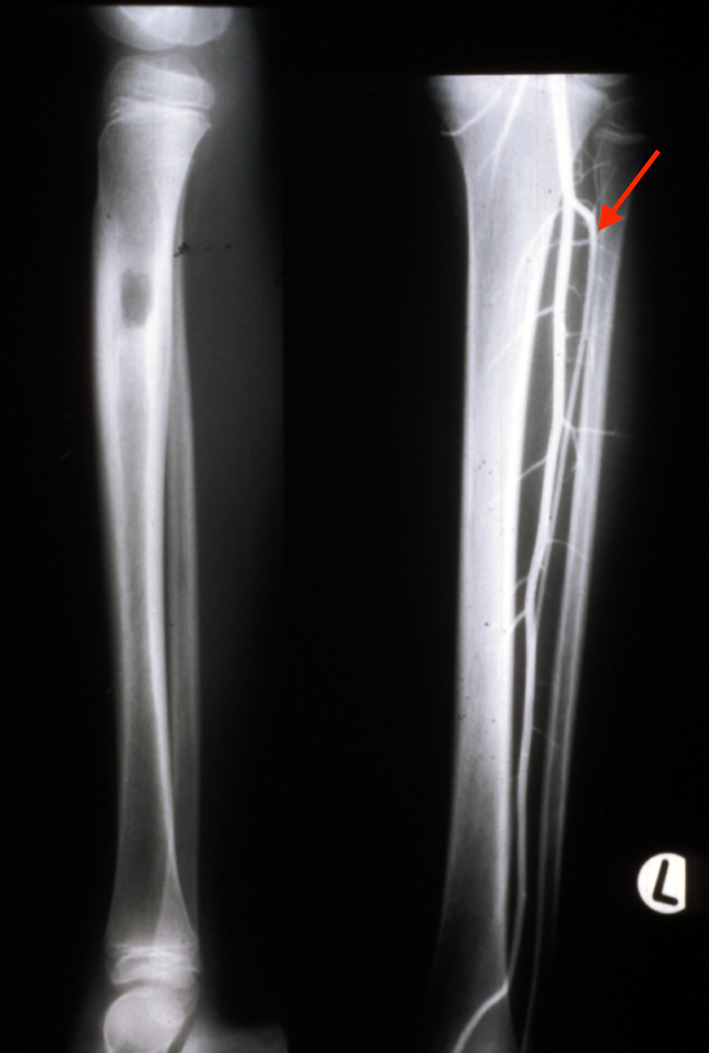

In 1983, a nine-year-old girl presented with a Ewing’s tumour of the right tibial diaphysis (Figure 10 left). She was treated initially with chemotherapy for 12 months with a good result. Segmental resection of the tibia was contemplated and we were invited by Ian Torode and Bob Dickens to consider a fibula reconstruction at the Royal Children’s Hospital Melbourne. Preoperative angiography however, revealed a single peronea magna supplying the foot in the other donor leg. The anterior tibial artery was diminutive (Figure 10 right) but was considered to be of a sufficient size to nourish the fibula transplant.

These studies revealed a reliable blood supply to the proximal epiphysis and the proximal two-thirds of the diaphysis from the anterior tibial artery (Figure 8A). The branches to the epiphysis from this artery were provided by the recurrent genicular artery and several short vessels arising from the anterior tibial as it passed forward beneath the tibiofibula joint (Figure 8D). Although the peroneal artery provided the dominant supply to the shaft of the bone via its nutrient and musculoperiosteal branches, its contribution to the head of the fibula was scanty (Figure 8B). Finally, the vascular anatomy to the leg was examined in 100 clinical angiograms revealing 21 limbs with anomalies, including two cases with a peronea magna (Figure 9).